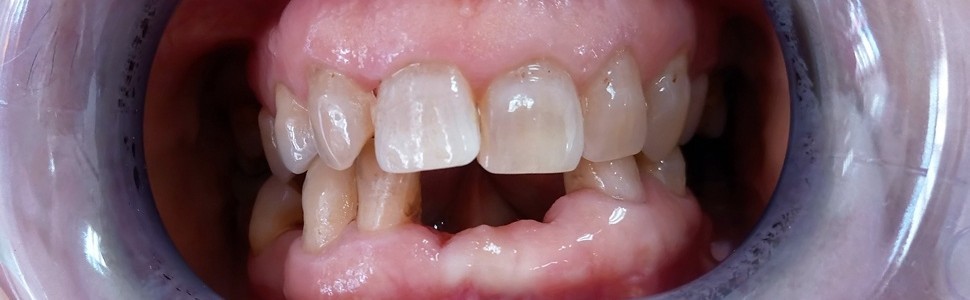

Dentin dysplasia type I – case report

W pracy przedstawiono definicję, charakterystykę i podział rzadkiej choroby genetycznej – dysplazji zębiny. Pośród dysplazji zębiny wyróżnia się niecałkowity rozwój zębiny typu II, dysplazję zębiny typu I, dysplazję zębiny typu II oraz włóknistą dysplazję zębiny. Opisano rozpoznanie i leczenie choroby u 49-letniej pacjentki.

The study presents definition, characterization and classification of a rare genetic disorder – dentin dysplasia.

Researchers distinguish several forms of dental dysplasia, such as dentinogenesis imperfecta type II, dentin dysplasia type I, dentin dysplasia type II and fibrous dentin dysplasia. In the article we describe diagnosis and treatment of the disease in a 49‑year-old female patient.